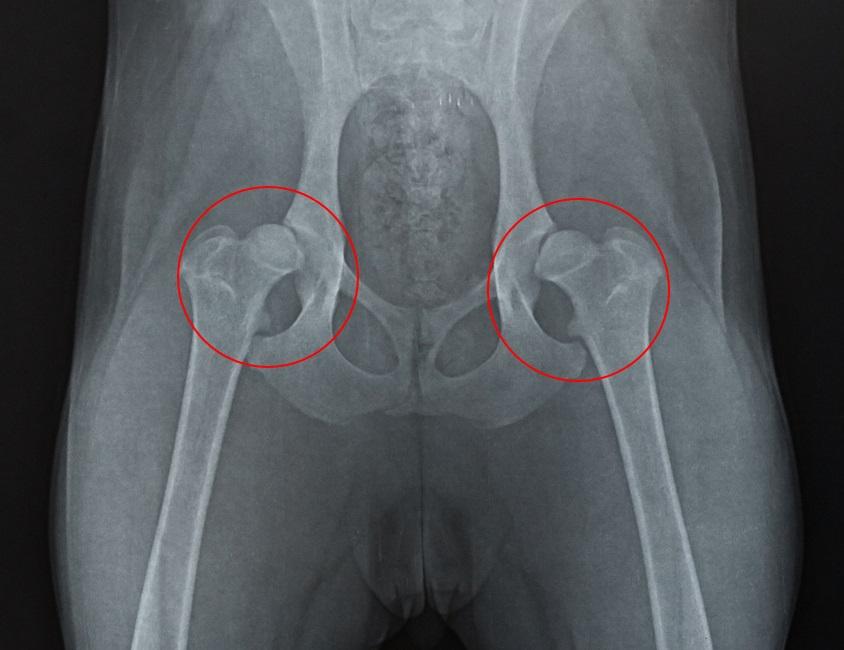

• Displasia de cadera: esta es una malformación congénita que se produce cuando la articulación que une el fémur no encaja con el hueso de la pelvis. Sucede durante el crecimiento del animal, donde la cadera se va desplazando hacia los laterales impidiendo que el perro se mueva de manera adecuada y se vuelve más grave con el tiempo. A pesar de ser bastantes los perros que sufren este problema, en la mayoría de casos no llega a desarrollarse hasta el final, pero si lo hace notaras que tu mascota cojea y sufre dolor al realizar actividades tales como correr, sentarse o subir la escalera.

Dependiendo de la causa que esté produciendo dolor de cadera a tu perro se puede tratar de forma médica, con o sin cirugía. Se recomienda acudir al veterinario si observas algún síntoma descrito anteriormente para que realice una radiografía y detecte cuanto antes el problema, sobre todo si se trata de displasia de cadera, ya que cuando antes se detecte, más fácil y rápido será su tratamiento y mejora. Así, estos son los tratamientos para el dolor de cadera en perro según su causa, aunque no son los únicos y siempre será el veterinario quien indique cuál es la mejor opción para cada paciente:

• Dislocación de cadera: igual que en el caso anterior, una dislocación de cadera puede requerir una operación o no dependiendo del tipo de luxación. En la mayoría de casos el veterinario, tras hacer radiografías e incluso ecografías, puede recolocar la parte de la zona de la cadera que se ha dislocado e inmoviliza la zona para que la articulación termine sanando sola.